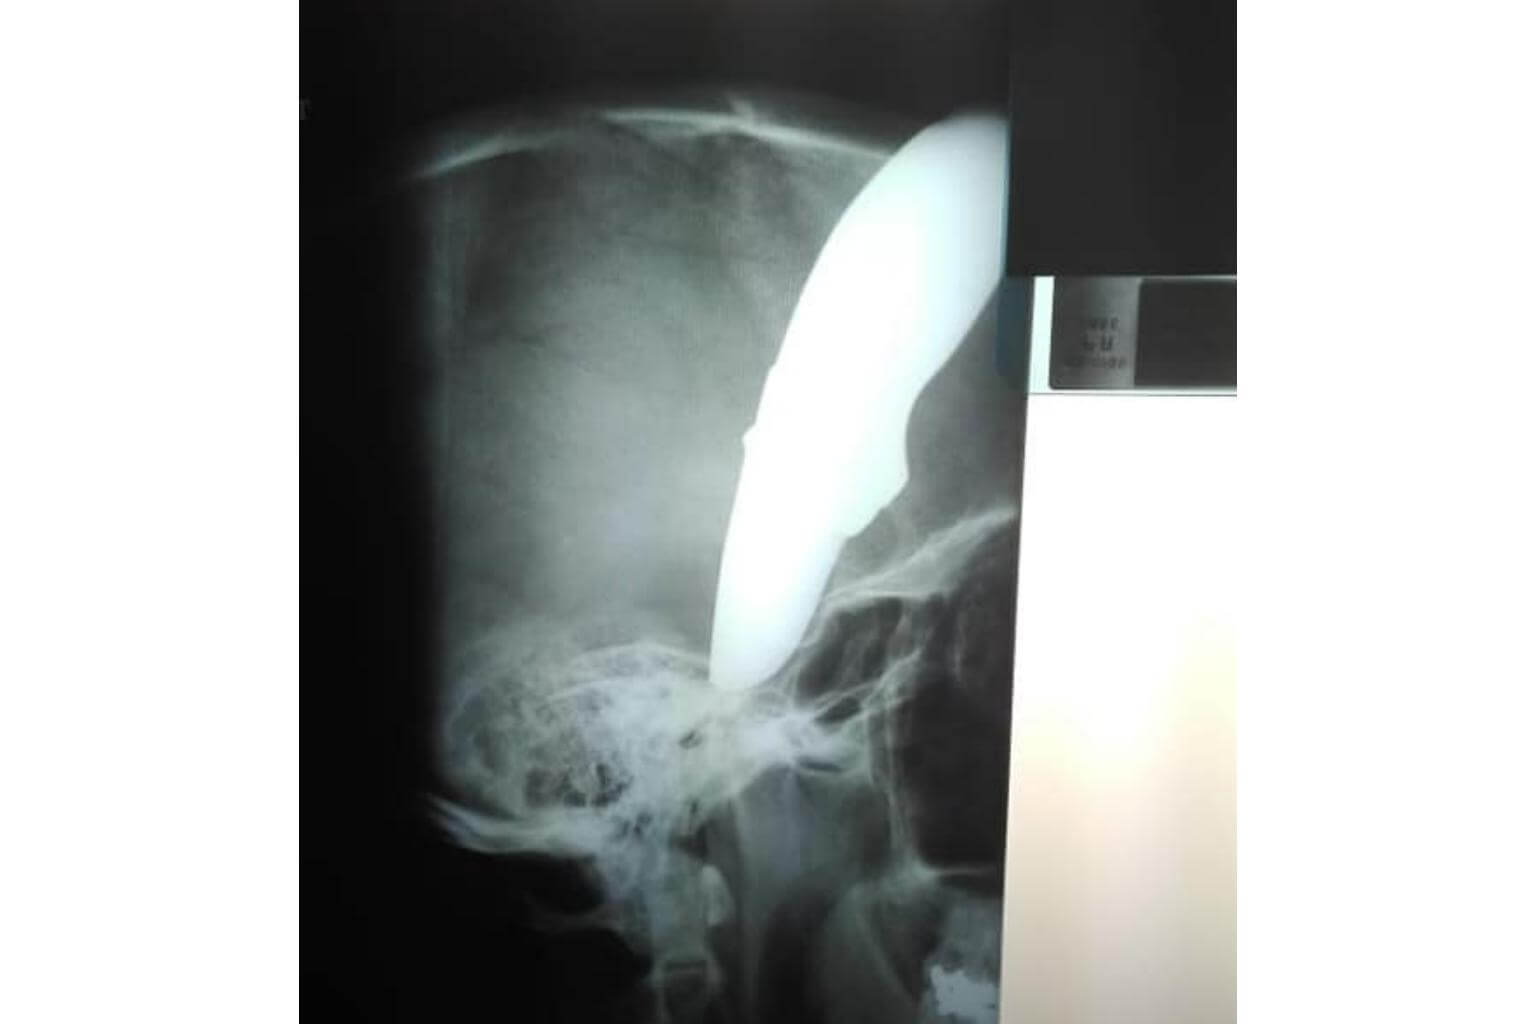

Dr Venter said: "(Mr Wayne) was very lucky in that although the knife was plunged into his skull, it bent on impact with the bone and the blade went down his face outside the skull."

Photographs of Mr Wayne, one of him looking calm while bleeding from the knife in his head at the doctor's and another of an X-ray of his head, have made the rounds on social media.